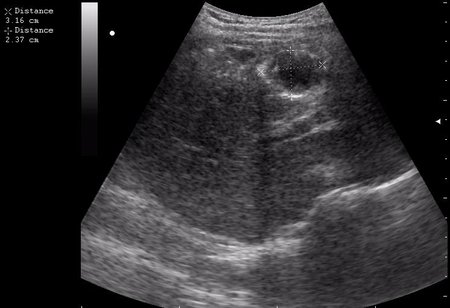

эхинококкоз печени девочка 12 лет.